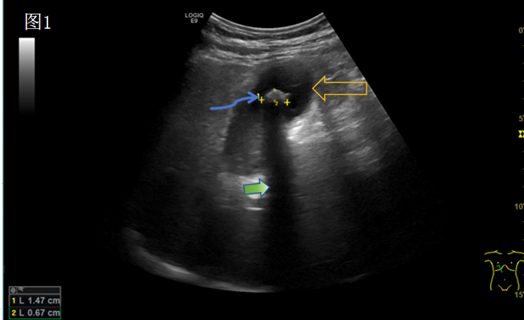

胆囊超声图像:黄色空心长箭头指的是胆囊,蓝色长箭头指的是胆囊结石(强回声光团),绿色箭头指的是强光团后方的声影。